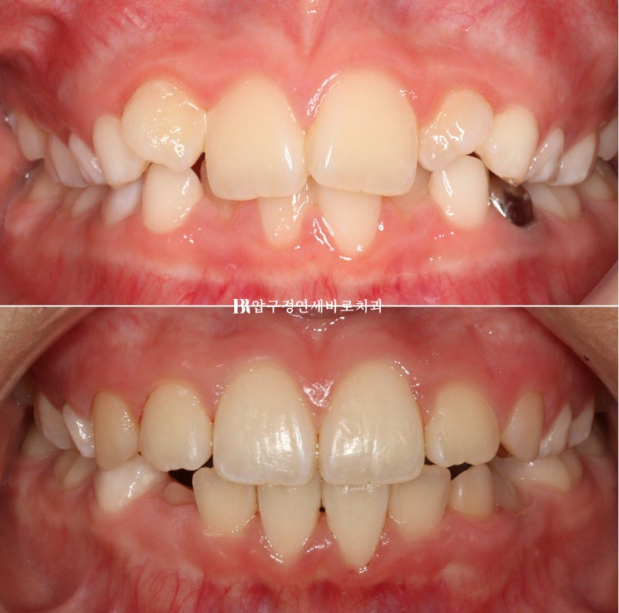

22.11.23

병원에 처음 온 날 모습입니다.

문제점을 나열해보자면

과개교합 (앞니가 깊게 물림)

덧니 (삐뚤빼뚤)

후속 영구치가 나올 공간 부족

2022.11~2024.06

첫장치는 43개였고 두번째는 17개였으니 총 60개의 장치 5일씩 착용했던 아이니까 300일의 총 치료기간입니다.

그리 길지 않은 기간이지만 치료계획이 적절하고 장치만 잘 껴준다면 인비절라인 퍼스트로 소아교정을 했을 때 결과가 아주 좋습니다.